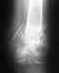

Разрыв ПКС и медиального мениска

Почему не оперируют? Назначили консервативное лечение на 2 месяца, затем ЛФК, массаж для тренировки 4-х главой мышцы бедра ещё на 3 месяца. Не будет ли поздно через 5 месяцев оперировать? И будут ли вообще делать операцию? Лечащий врач ничего не объясняет. Я консультировалась у других травматологов, они говорят надо оперировать и я только теряю время. Что мне делать?

Девушка, у меня был первоначально разрыв ПКС. т.к. стояла долго в очереди, ещё со временем и мениск порвала внутренний. операцию сделали через 2,5 года и ни чего, дожила. считайте за счастье сделать операцию за пол года..